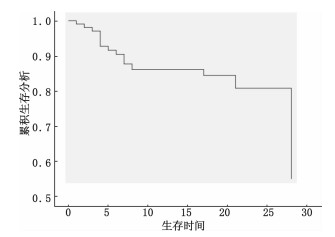

入选患者28 d内共死亡25例,死亡原因分别为多器官功能障碍10例,循环衰竭11例以及中枢功能障碍导致的死亡4例。对58例患者进行COX分析之后发现,患者APACHE Ⅱ评分[OR: 1.08; (95% CI:1.03 to 1.14)]、Synek评分>2[OR: 0.17; (95% CI: 0.03 to 0.80)]、是否出现痫样波[OR: 23.70; (95% CI: 2.02 to 277.73)]以及电节律减慢[OR:8.54; (95% CI :1.72 to 42.32)]与患者的28 d病死率独立相关,见表 3,其生存曲线见图 5。

| 图 5 脑电监测患者的生存曲线 Figure 5 Kaplan-Meier survival curves of patients with EEG monitoring |